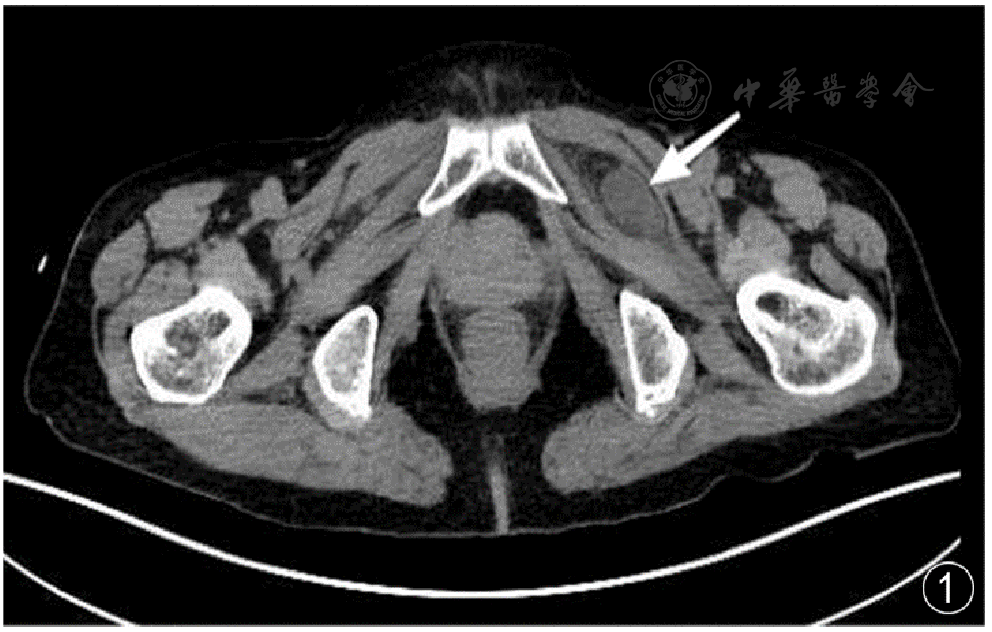

图1 耻骨肌和闭孔外肌之间嵌顿肠管(箭头所指)